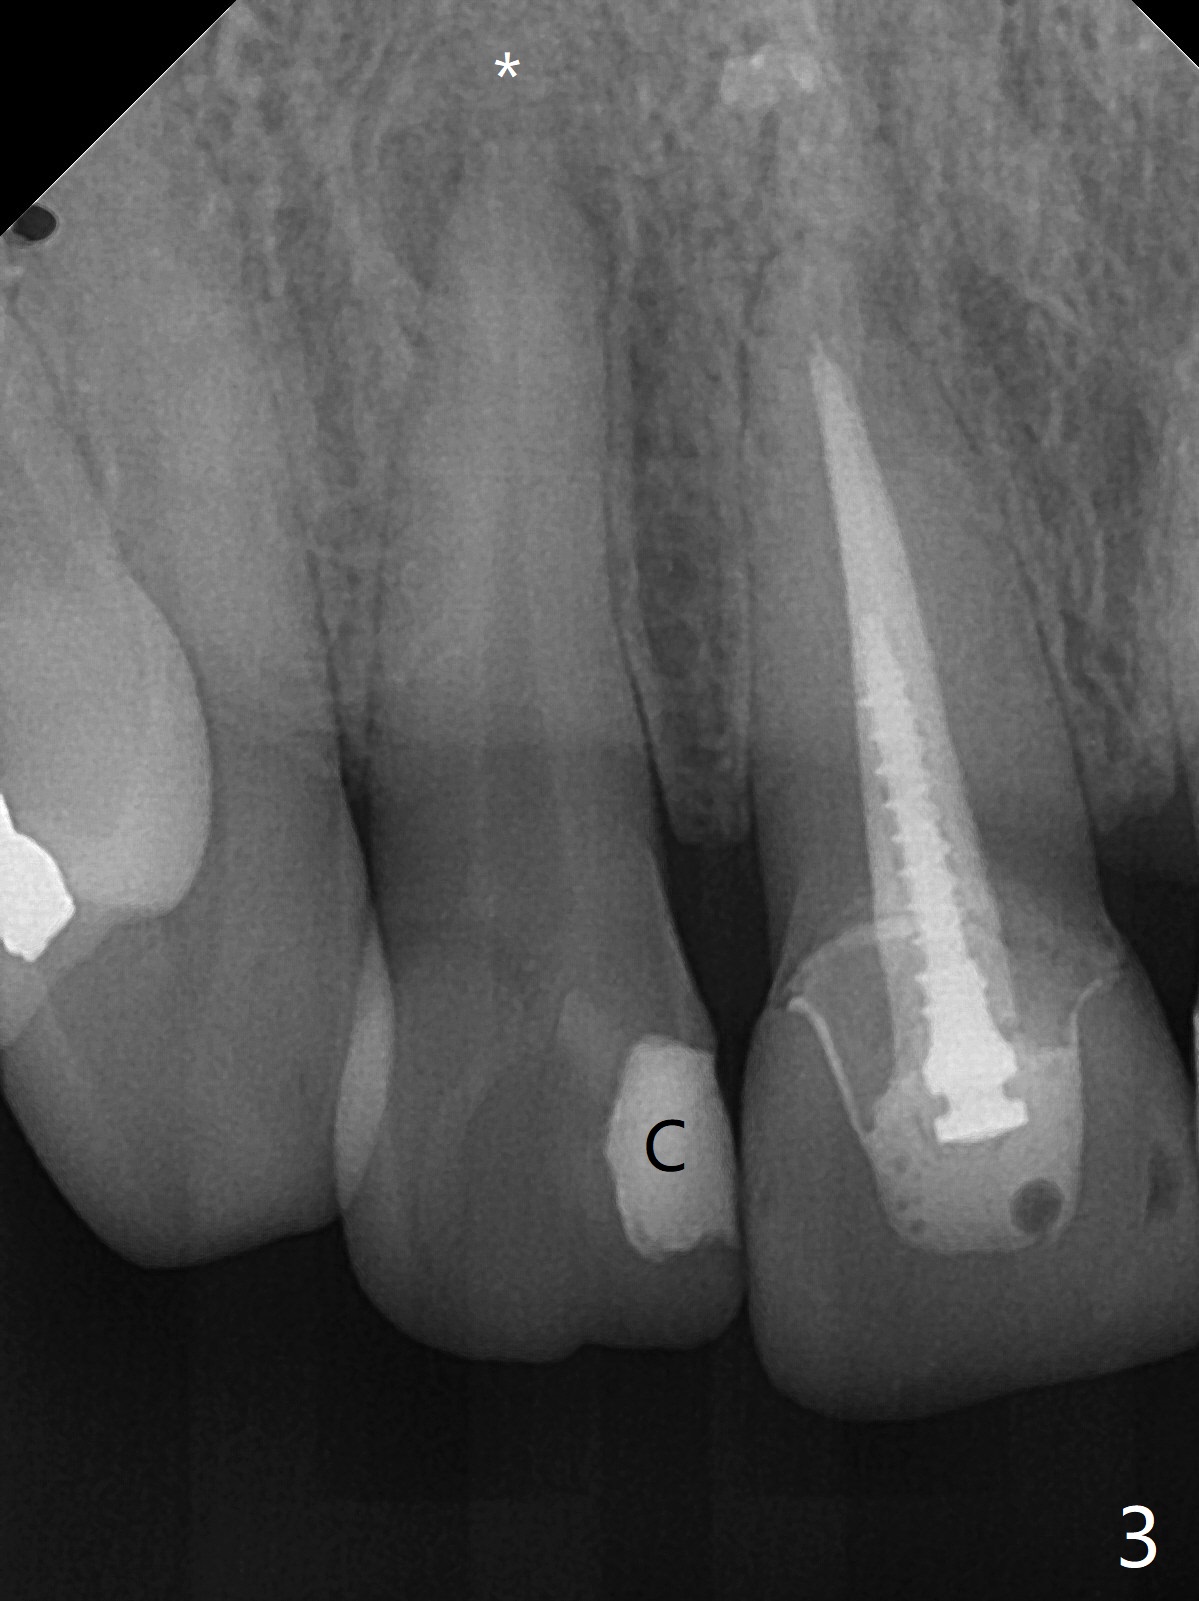

A 46-year-old woman requests a crown for the discolored tooth #7 (Fig.1,2) with mesiolingual composite (Fig.3 C) and periapical radiolucency (*). After RCT (Fig.4,5) with sodium hypochlorite, the tooth #7 is whiter than the ML composite (Fig.6,7). The patient returns 1 day post RCT for in house internal and external bleaching (Fig.8) with 35% hydrogen peroxide gel closed in the canal when she leaves. Three weeks later, the lateral incisor has the shade as the neighboring natural teeth (Fig.9,10). After the lightest shade composite placed in the canal and the access hole (Fig.11), the lateral looks better than the central with a crown and cervical discoloration (Fig.12).